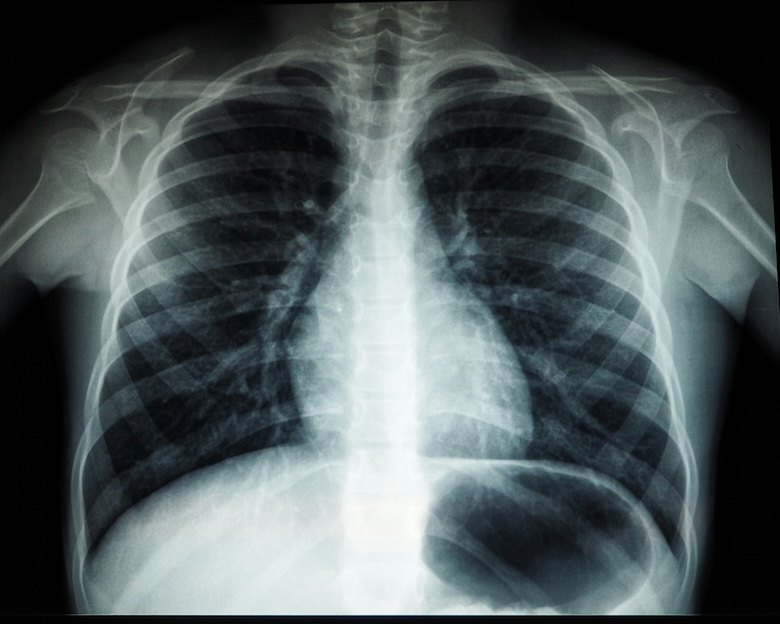

Medical imaging refers to the method and procedure of generating visual depictions of the body’s interior for clinical examination, medical intervention, and the visual portrayal of organ or tissue functionality. This technique is utilized to expose internal structures, diagnose and treat illnesses, and create a reference database of standard anatomy and physiology to detect anomalies. X-rays, CT (computed tomography) scans, ultrasounds, MRI (magnetic resonance imaging), and nuclear medicine imaging are typical examples of medical imaging techniques. Medical imaging has evolved into a crucial instrument for diagnosing various health conditions such as trauma, cancer, cardiovascular diseases, and neurological disorders. It forms an essential component of biological imaging encompassing diverse technologies like X-ray, CT scan, MRI scan, PET scan, and ultrasound. Highly skilled technicians ranging from oncologists to internists employ medical imaging; it is a fundamental aspect of contemporary healthcare science.

Highlighting Thoracic Complications and Conditions: AI-driven algorithms can expedite the detection of conditions like pneumonia and pneumothorax, facilitating prompt treatment decisions.